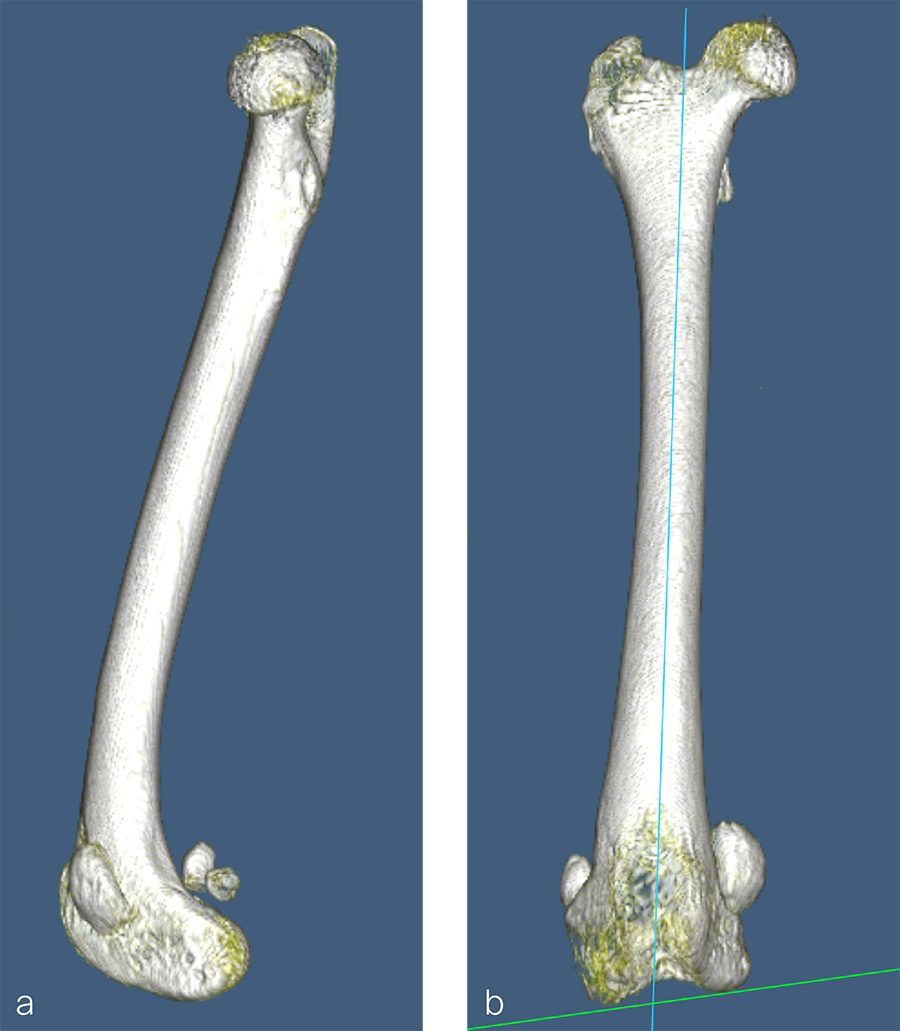

Fig 9a-b Preoperative CT 3D reconstruction of the right femur confirming distal femoral varus (anatomical Lateral Distal Femoral Angle was 104°). Planned correction was to perform a 10° lateral closing wedge ostectomy.